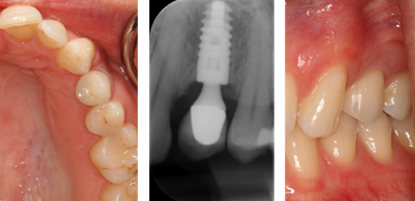

SINGLE DENTAL IMPLANT

Those who have a single tooth missing often choose Dental Implants for replacement as it comes closest to imitating a natural tooth. Implants are also long-lastingly sturdy since they are fused to the jawbone and can stably stand on their own. Dr Bopanna offers uncompromising attention to detail, and uses the latest equipment to craft your new tooth.

Single tooth replacement is normally carried out in three stages. The failing tooth is extracted and an implant is placed into the socket or it can be placed after complete healing has occurred (3 months). After allowing the bone and gum to heal around the implant a scan body is attached to the implant/s and a 3d digital impression is taken. The scan is then uploaded to either Atlantis or Exocad and the abutment is designed, after which the stl file(3D file) is used to design the crown which fits on top of the implant. All of these stages can be carried out in the single appointment depending on need and condition of the patient.

CROWN FITTED

Card image Actual Practice Photographs ©Dr.Pavan Bopanna